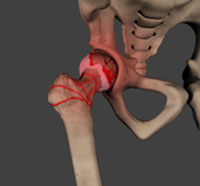

Avascular necrosis, also called osteonecrosis is a condition in which bone death occurs because of inadequate blood supply to it. Lack of blood flow may occur when there is a fracture in the bone or a joint dislocation that may damage nearby blood vessels.